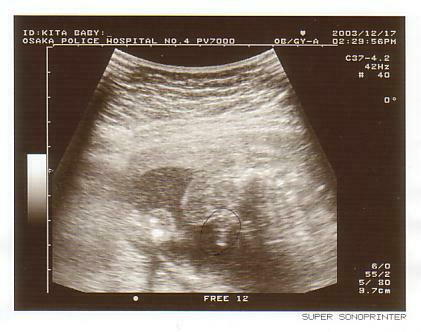

<第二回超音波検査>

10月1日、第二回目の超音波検査です。前回の超音波検査で

は黒い袋しか写っておらず、あまり実感はありませんでしたが、

今回の写真ではかなり人?の形がわかるような感じです。

小さな頭と両手が写っており、実際の超音波の映像ではピクピ

クと動いていたそうです。

この写真を見てかなり実感がわき、感動したのを覚えてます。

この時は画面上で体長を測っていませんが、俊介は約3cmく

らいです。

この日に俊介の出産予定日は5月7日と決まりました。